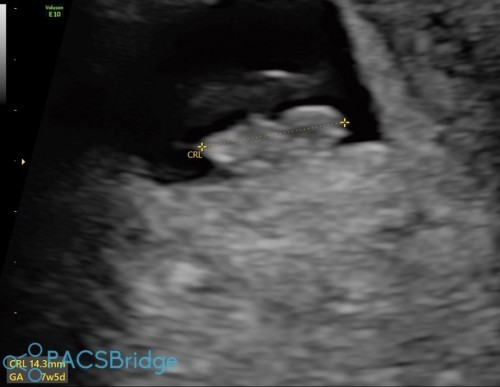

วันนี้แม่ ลุ้นมาก ว่าแม่จะได้เห็นนู๋ มั้ยน๊าาาาา เพราะ อายุครรภ์ยังน้อยมาก จากที่ ซาว อายุครรภ์เพียง 7 สัปดาห์กว่า แต่ในที่สุด เราก็ได้เจอกันนะเจ้าตัวเล็ก🧡